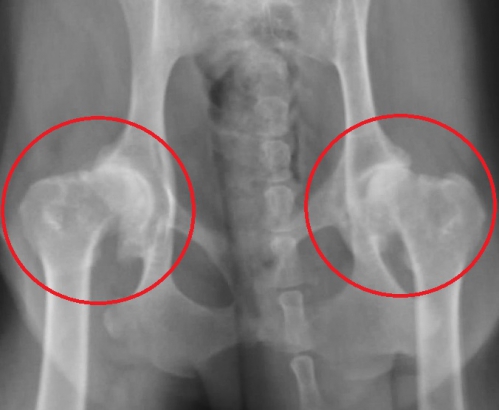

変形性関節症の診断は、問診、触診、レントゲン検査などにより行われます。初期には明らかな徴候を示さないことも多いですが、病状の進行に伴い散歩や運動を嫌がったり、歩行の異常といった症状が見られるようになります。レントゲン検査では軟骨の評価が難しく、初期の病変を把握することは困難ですが、重症化するにつれて軟骨付着している骨の部分の硬化や骨棘(こつきょく)形成、炎症性の関節液による関節包の腫れなどの所見が見られるようになります。

下は股関節の進行した変形性関節症のレントゲン写真です。赤丸の中が股関節ですが、大腿骨頭は変形して、関節内には骨棘の形成がみられます。同じ部位の正常写真が右です。

このワンちゃんは日常的に下肢の痛みを訴えており、運動状態によって、また寒い時期に悪化がみられます。後ろ足には常に痛みがあり、充分に動かすことができません。